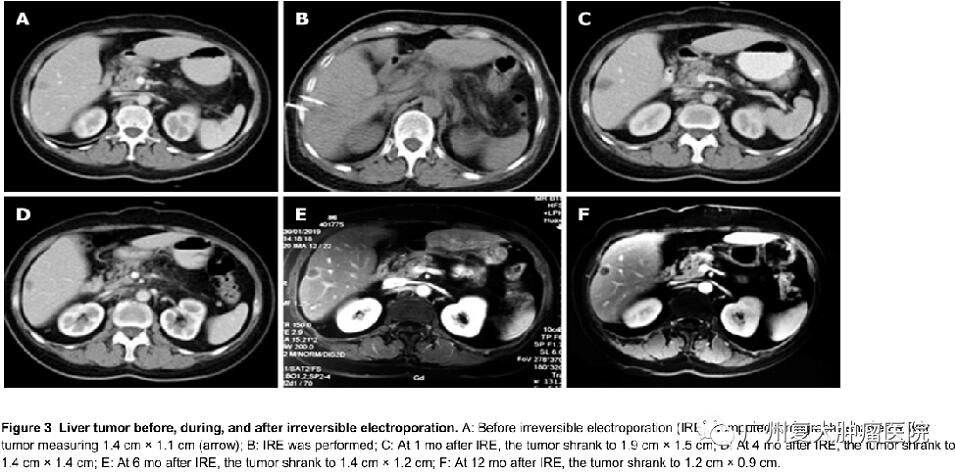

当然,纳米刀相关机制、理论、最佳的参数以及其治疗的安全性和疗效还需要进一步研究及更多的循证医学证据。纳米刀治疗肝癌,因其无热吸除效应,可完全消融临近下腔静脉、大肝动脉或门静脉结构的肿瘤,且不损伤这些重要结构。对治疗靠近肝门区、血管、胆管等重要结构的肝肿瘤较传统的消融方法具有明显的优势。